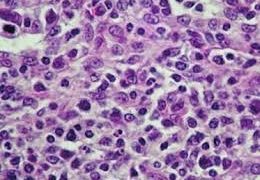

C  ニワトリの病気

ニワトリの病気  ニワトリの病気

ニワトリの病気  ニワトリの病気

ニワトリの病気